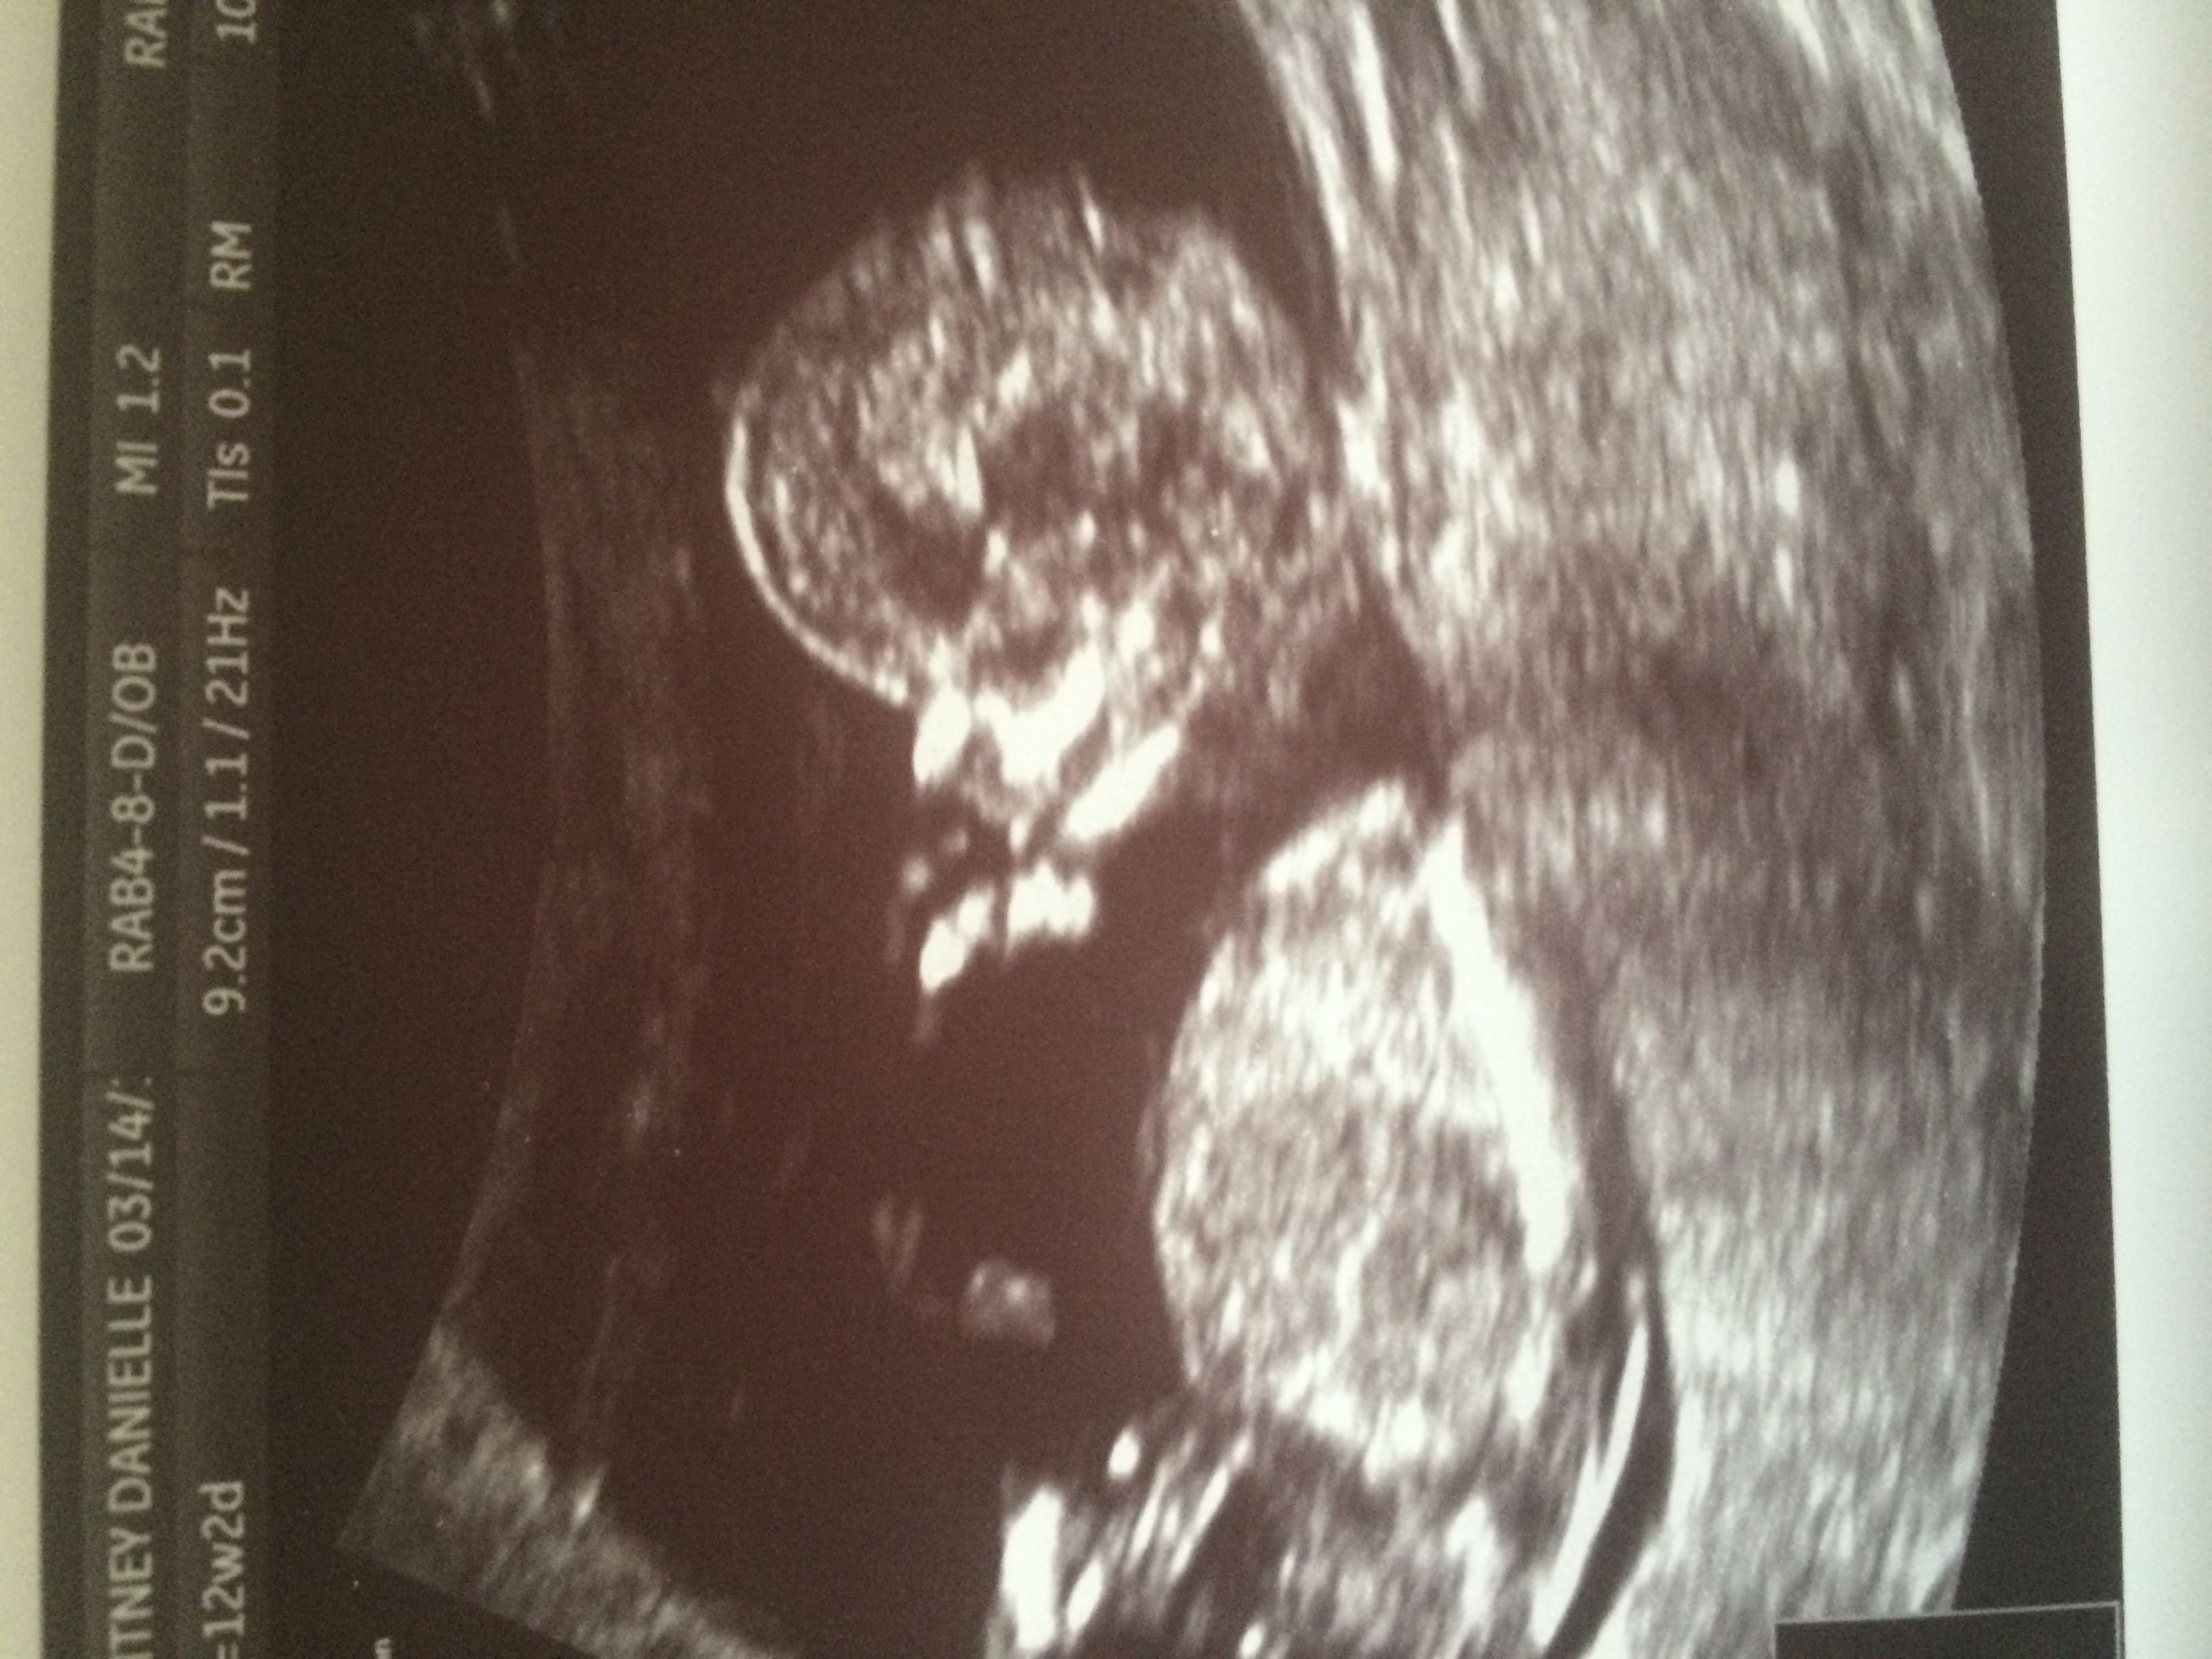

I am so happy! Had an ultrasound at 12w2d today, after losing last pregnancy in a MMC. Baby was kicking and doing really well, measuring at 12w6d! I just feel like I can finally breathe, being over the milestone of when we lost LO last time.